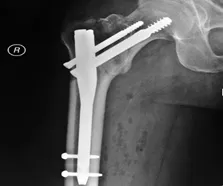

Il existe plusieurs opérations chirurgicales pour soigner une fracture du col du fémur :

- L’ostéosynthèse : C’est le fait d’insérer une vis pour stabiliser la fissure du col du fémur, à condition que la densité osseuse soit suffisante.

-

Le vissage dynamique de la hanche : C’est une plaque de métal qui est placée dans la partie supérieure de la jambe accompagné d’une vis fixée sur la tête du fémur.

- La prothèse de la hanche : Cette intervention est très régulièrement utilisée pour les personnes âgées; elle consiste à remplacer le col du fémur fracturé par une prothèse.